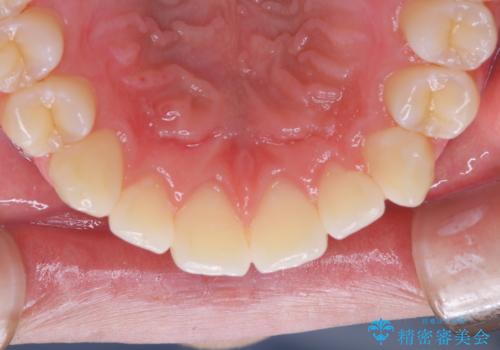

染め出しをして磨き残しのチェックと歯のクリーニング

染め出し液を使ってプラークを染め出すことにより、普段の歯みがきで磨き残している場所を目で確かめることができます。

日々の歯磨きを上達するには、まずどこが磨けていないか認識することが大切です。